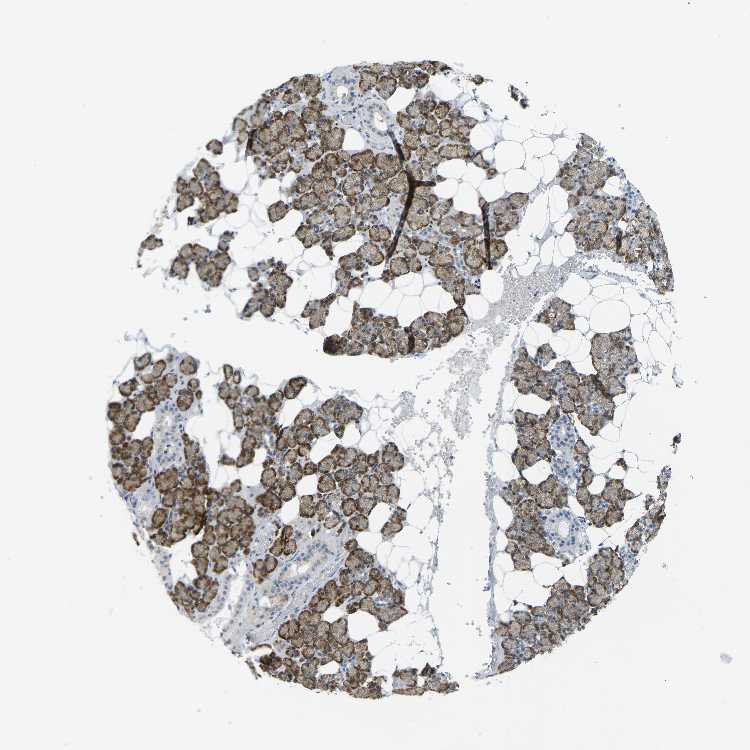

SALIVARY GLAND - Antibody stainingi

Antibody staining in the annotated cell types in the current human tissue is reported as not detected, low, medium, or high, based on conventional immunohistochemistry profiling in selected tissues. This score is based on the combination of the staining intensity and fraction of stained cells.

Each image is clickable and will lead to virtual microscopy that enables deeper exploration of all samples and also displays staining intensity scores, fraction scores and subcellular localization as well as patient and tissue information for each sample.

Antibody HPA002529Antibody HPA002632Antibody CAB019323

Glandular cells HighHighHigh